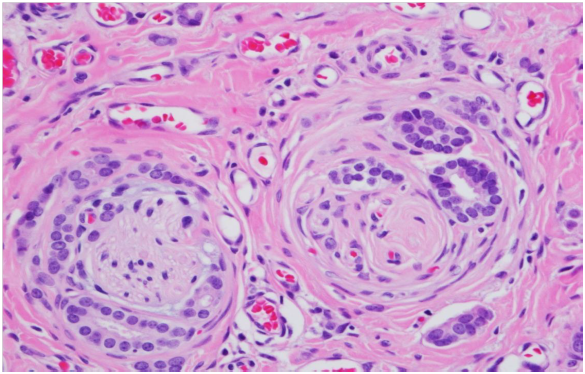

We report a case of a 63 year old female, with history of Stage I right breast invasive lobular carcinoma diagnosed twelve years previously, status post bilateral mastectomies with tram flap placement from the thigh. She has no history of familial breast cancer. She presents with a right chest wall nodule. The chest wall incisional biopsies and right breast tram pedicle needle core biopsies reveal invasive well differentiated ductal carcinoma grade 1 (Nottingham score, 1 + 2 + 1 = 4). The patient undergoes right tram flap mastectomy measuring 16 x 15.5 x 3.1 cm in greatest dimensions and weighing 337 grams. The posterior surface of the specimen displays strips of skeletal muscle fibers. The cut surface shows linear gray white fibrous area measuring 4.7 cm in length and 2.5 cm in diameter corresponding to the tracking scar of the needle core biopsy, involving the upper inner quadrant and abutting the posterior surface. Well differentiated glands extend into the pectoralis major muscle fibers (Figures 1 & 2). The invasive ductal carcinoma grade 1 (Nottingham score, 1 + 2 + 1 = 4) is seen in all sections from the tracking scar, which measures 4.7 cm in greatest dimension (Figure 4). The invasive ductal carcinoma demonstrates perineural involvement (Figure 3), vessel wall invasion and microcalcifications. The focal residual breast tissue shows fibrocystic change, atrophy and biopsy site changes (Figures 5 & 6).

Our patient, a 63 year old female, had a history of right sided stage 1 invasive lobular carcinoma. She had bilateral mastectomies with prophylactic simple mastectomy of the left breast and tram flap replacement. Twelve years later, she presents with a right sided chest nodule. The chest wall incisional biopsies and right breast tram pedicle needle core biopsies reveal invasive well differentiated ductal carcinoma grade 1 (Nottingham score, 1 + 2 + 1 = 4) (Figure 4). The subsequent right tram flap mastectomy shows well differentiated glands involving the pectoralis major muscle (Figures 1 & 2), perineural extension (Figure 3), vessel wall invasion, and microcalcifications. The tumor measures 4.7cm in the greatest dimension. The residual breast tissue shows fibrocystic changes, biopsy site changes and skeletal muscle atrophy (Figures 5 & 6).

Figure 2 Well differentiated glands involving skeletal muscle fibers, H & E (x400).